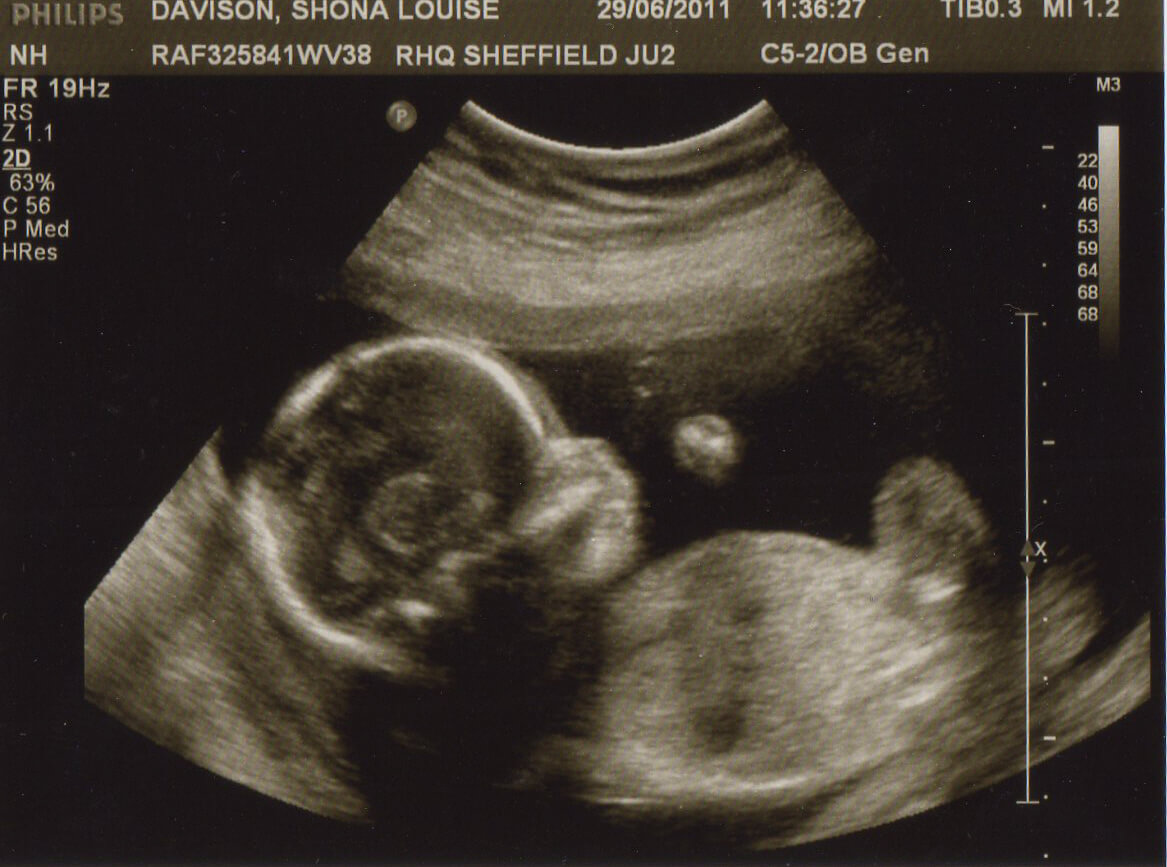

УЗИ и анализы: нормы на 20 неделе

На 20 неделе необходимо сдать мочу (перед визитом к гинекологу) и пройти ультразвуковое обследование.

УЗИ на 20-24 неделях дает врачу следующую информацию:

- Размеры плода, по которым устанавливается срок беременности.

- Наличие пороков развития тела и внутренних органов малыша (особое внимание уделяется сердцу).

- Половую принадлежность крохи.

- Расположение, толщину и структуру плаценты.

- Количество околоплодных вод.

- Состояние шейки матки.

- Состояние кровообращения между маткой и плодом (эти данные получают с помощью доплера).